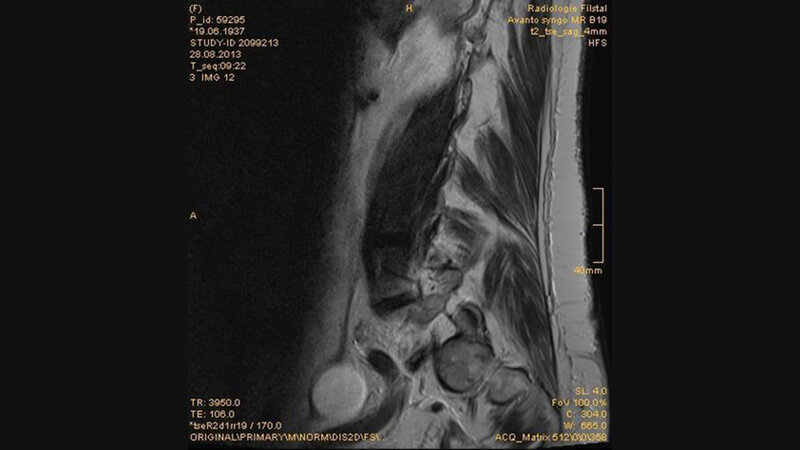

Ovarialzysten können als liquide Formationen im weiblichen Becken mit unterschiedlicher Größe bei kernspintomographischen Untersuchungen als Zufallsbefund erfasst werden.

Der transvaginale Ultraschall ist die Methode der Wahl in der Darstellung von Adnextumoren. CT und MRT sind ergänzende Untersuchungsmethoden. Ovarialzysten können akute oder chronische Beckenschmerzen verursachen.